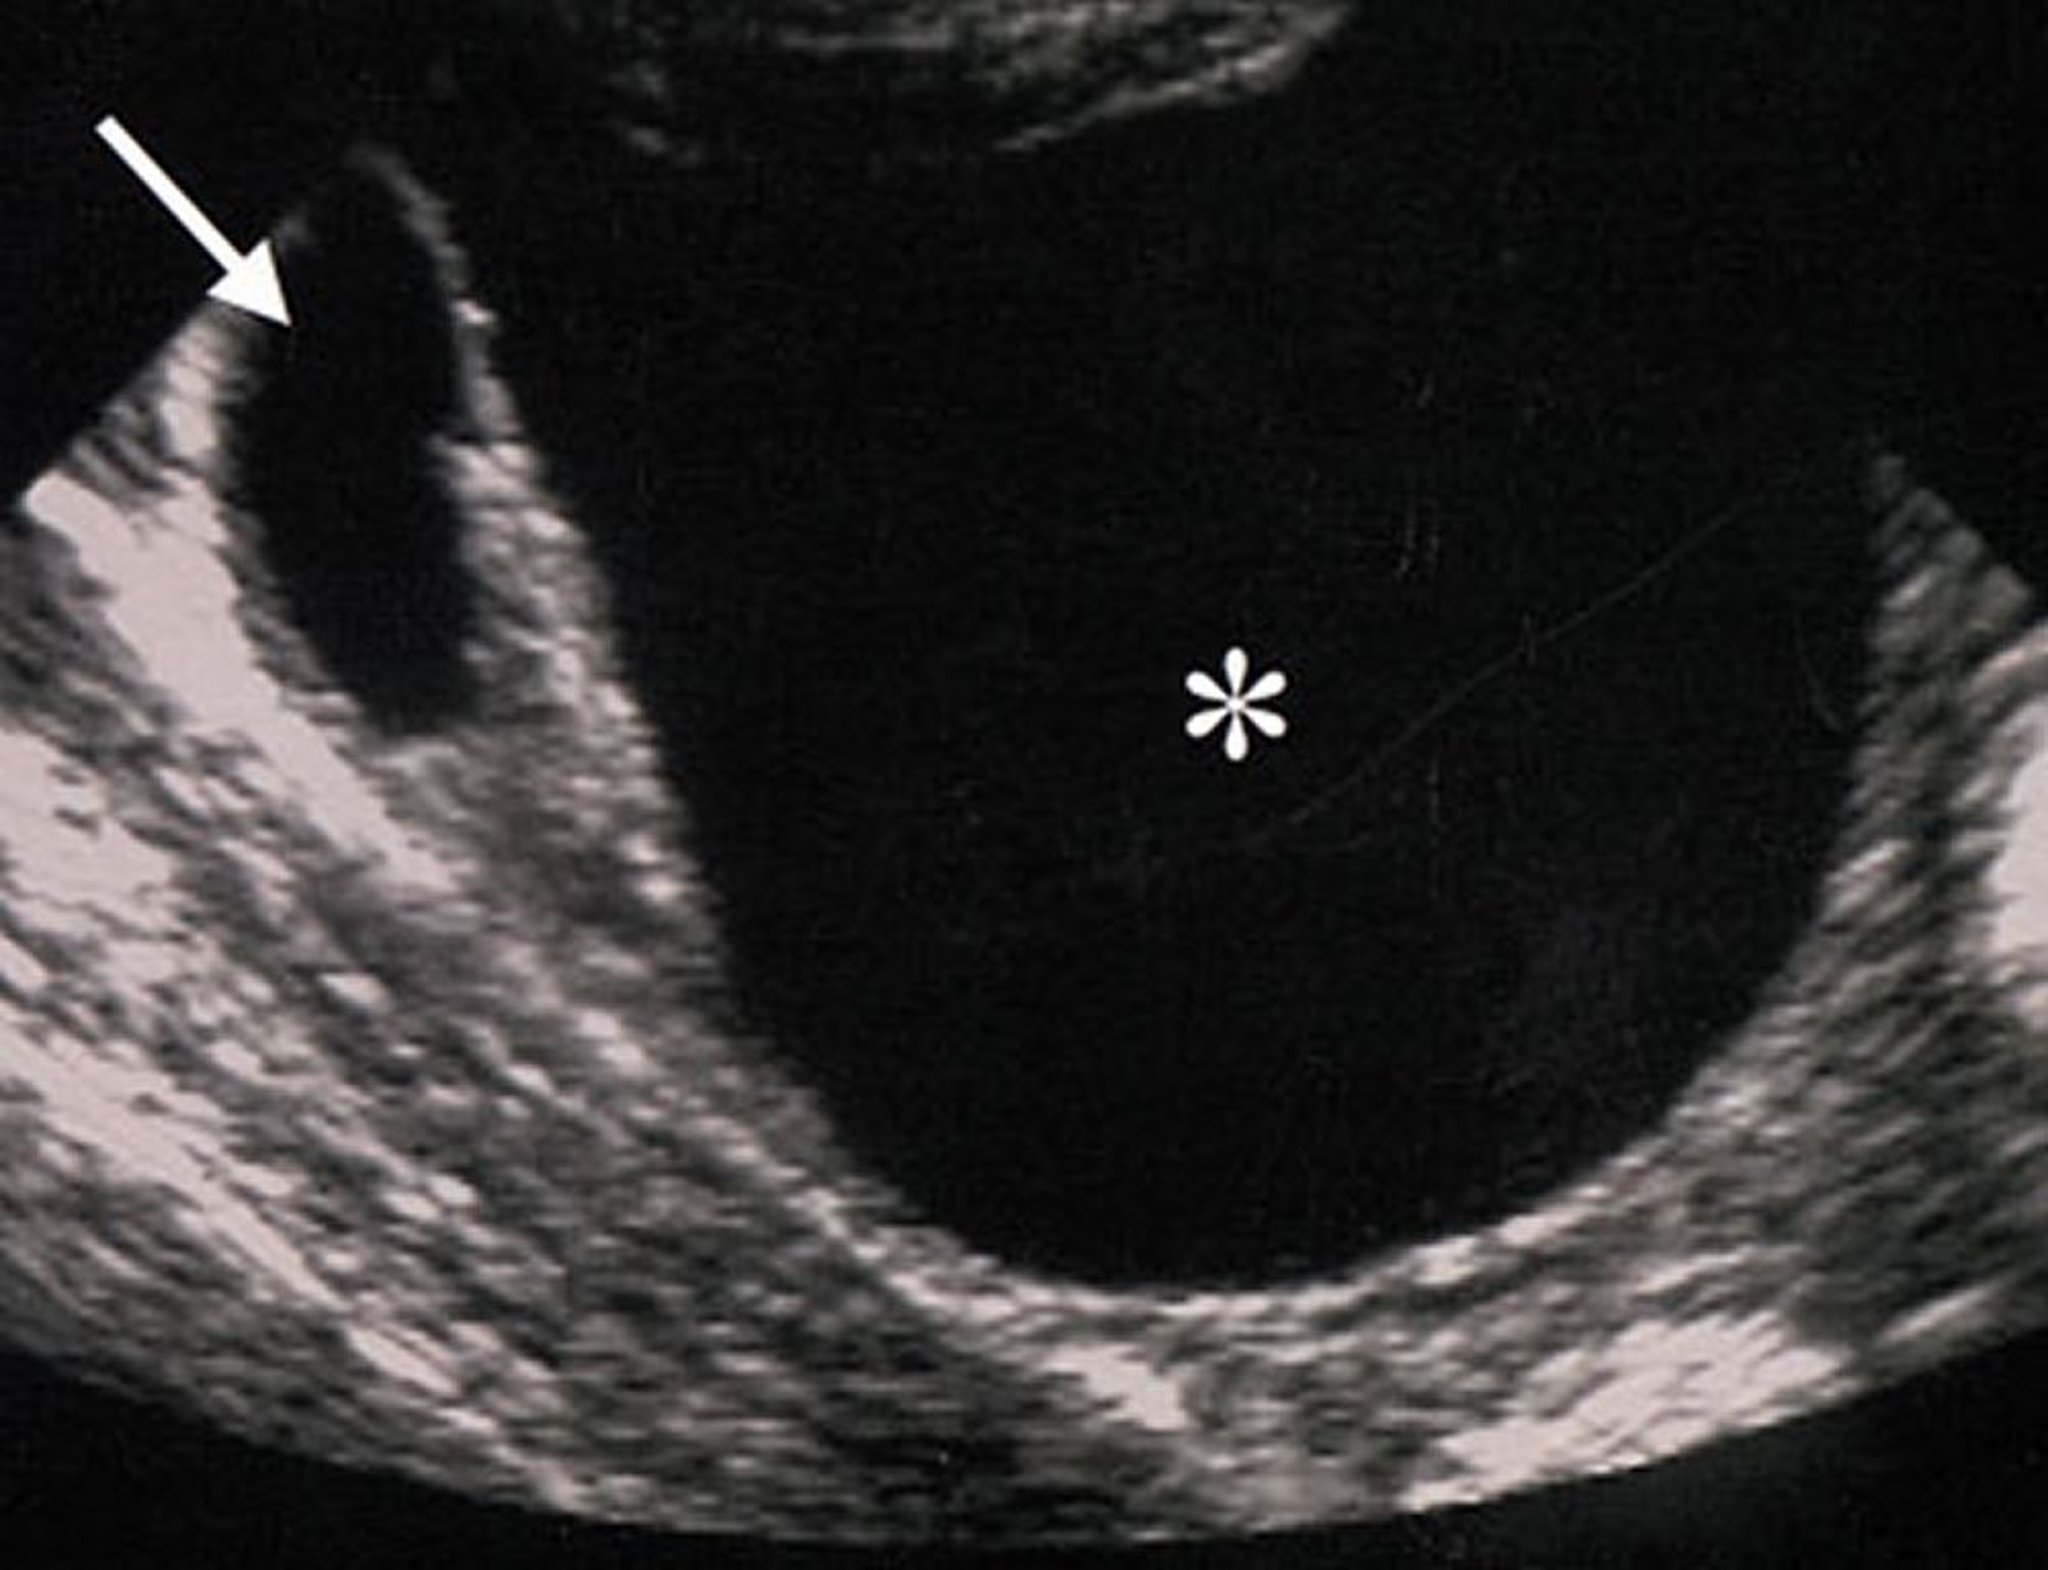

Échographie d'une masse ovarienne bénigne

Les caractéristiques échographiques de cette masse ovarienne (indiquées par un astérisque) suggèrent que la masse est bénigne. La masse est anéchoïque (ce qui suggère l'absence de composants solides), régulière, bien circonscrite et sans épaississement ou excroissances des parois.